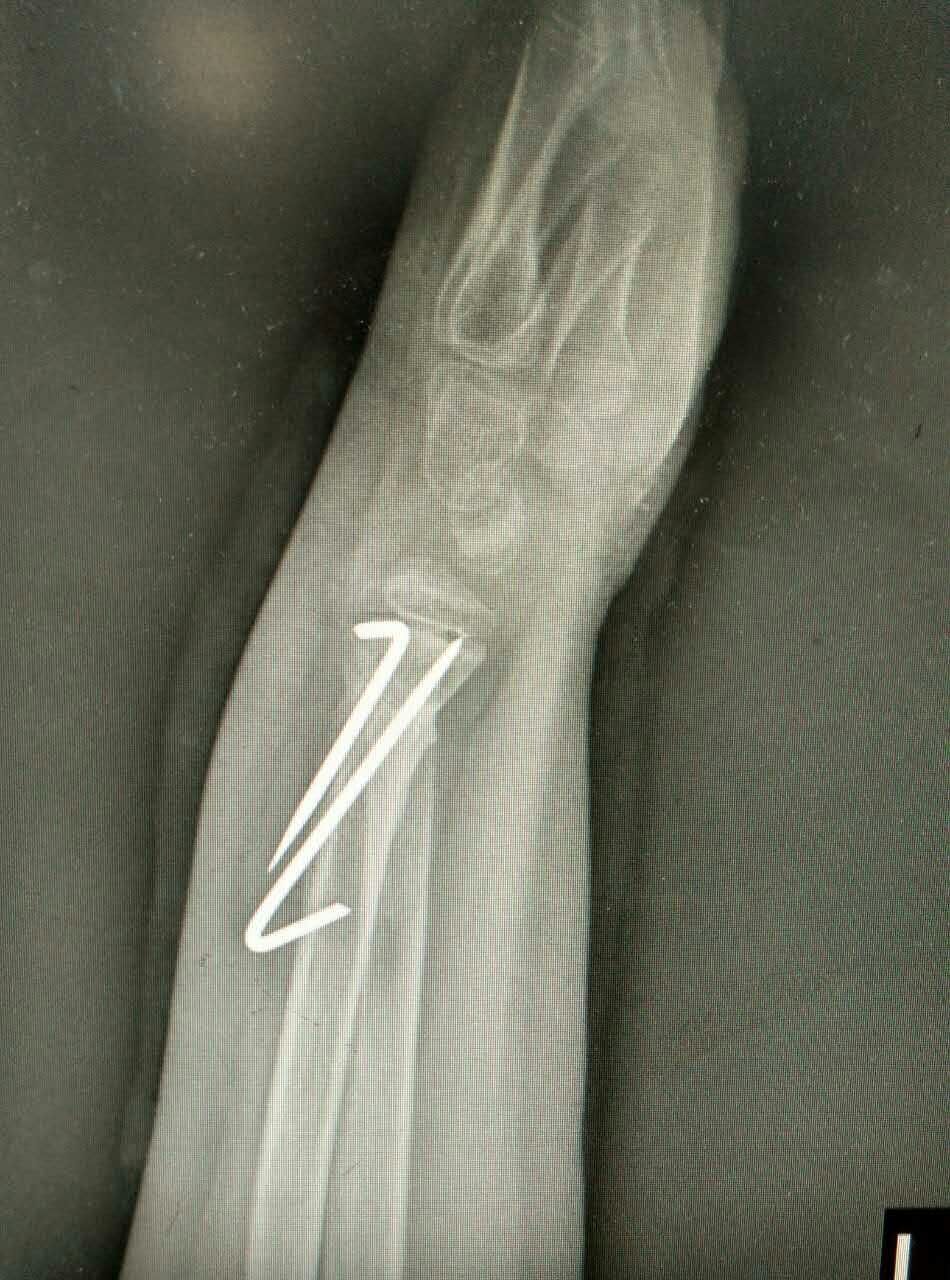

患儿,男,10岁,因左桡骨远端骨折畸形愈合5周来我院就诊。患儿家长曾在我市多家医院就诊,均认为切开复位,传统手术切口6-8cm。腕部血管、神经较多,共约20余条,稍有不慎,将给患儿造成较大后遗症,瘢痕永久存留,外观不美,且费用昂贵。我科谢瑞卿主任看过病人后决定采取微创闭合复位内固定,起初家属半信半疑,但后来经过耐心解释后决定在我院手术治疗。于2016-01-25在全麻下行左桡骨远端陈旧性骨折闭合复位内固定术,微创切口0.5cm左右,我们成功避免了各种意外事件的发生,截骨复位,我们巧妙应用骨刀在微创手术中的优点,成功闭合复位,术后复查拍片骨折复位满意。在骨科全体医护人员的积极治疗护理下,于春节前临床治愈出院。术后6周复查骨折已骨性愈合,腕关节功能良好。患儿家长万分感谢,赞叹西安凤城医院有如此精湛的技术和优质的服务质量与态度。

术前X光片